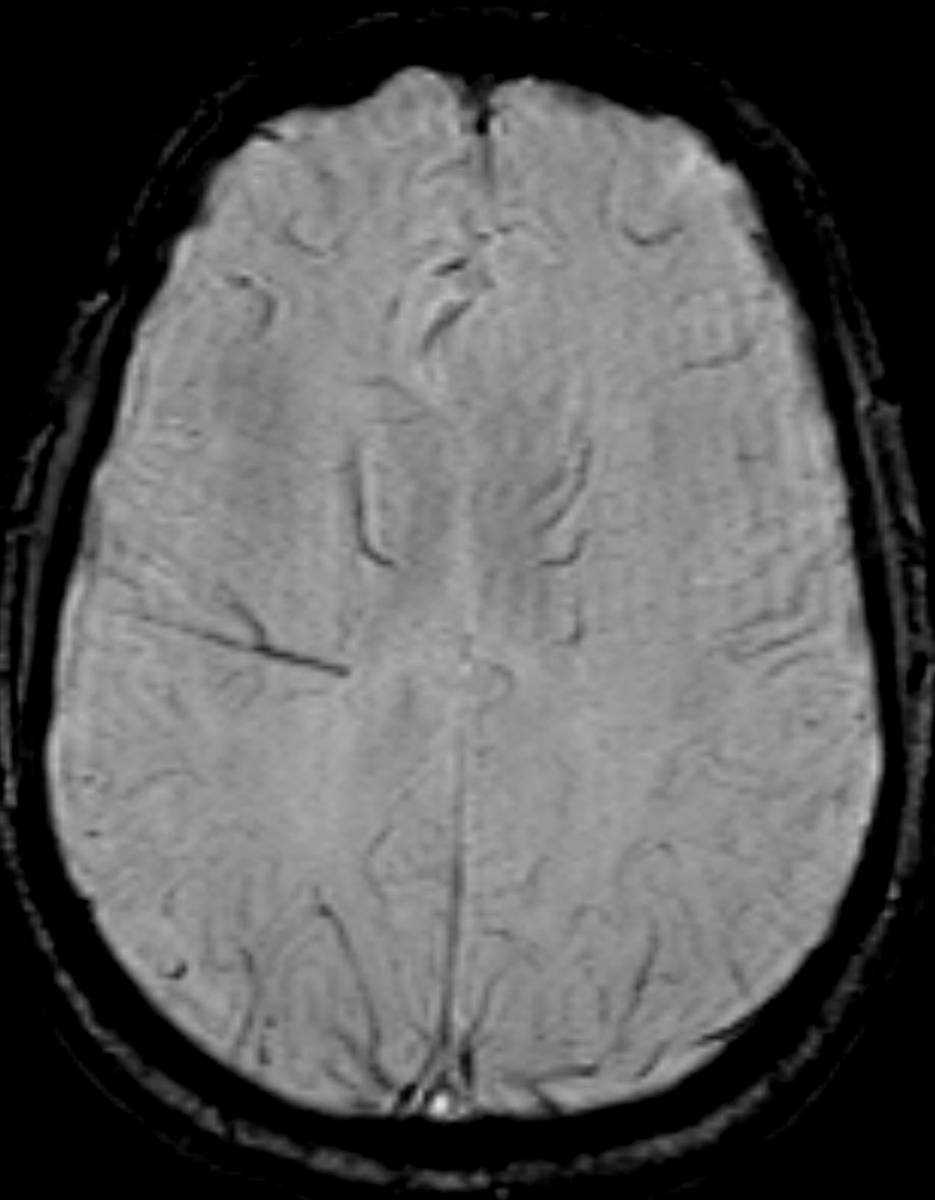

Callosal Agenesis

This is a case of agenesis of the corpus collosum in an otherwise asymptomatic 9-year-old male. The first three images demonstrate wide spacing and parallel orientation of the lateral ventricles with a colpocephalic appearance. Paralleling the medial margin of the body of the right later ventricle, there is a bundle of Probst on the right on the second image. The third ventricle is high-riding and communicates with a dorsal interhemispheric cyst, which is nicely demonstrated on the third image. The fourth image demonstrates a ‘sunray’ appearance of the sulci slightly off of the midline. The final two images demonstrate absence of the fornices and hypoplasia of the hippocampi. Collosal agenesis can occur as a primary agenesis or secondary dysgenesis. Primary colossal agenesis may be asymptomatic, occurring as frequently as 1:20,000 persons. There is a 2:1 male predilection. Agenesis of the corpus callosum may be seen as a component of Chiari II malformation, Dandy-Walker spectrum, grey matter heterotopia, holoprosencephaly and polymicrogyria, among many others.